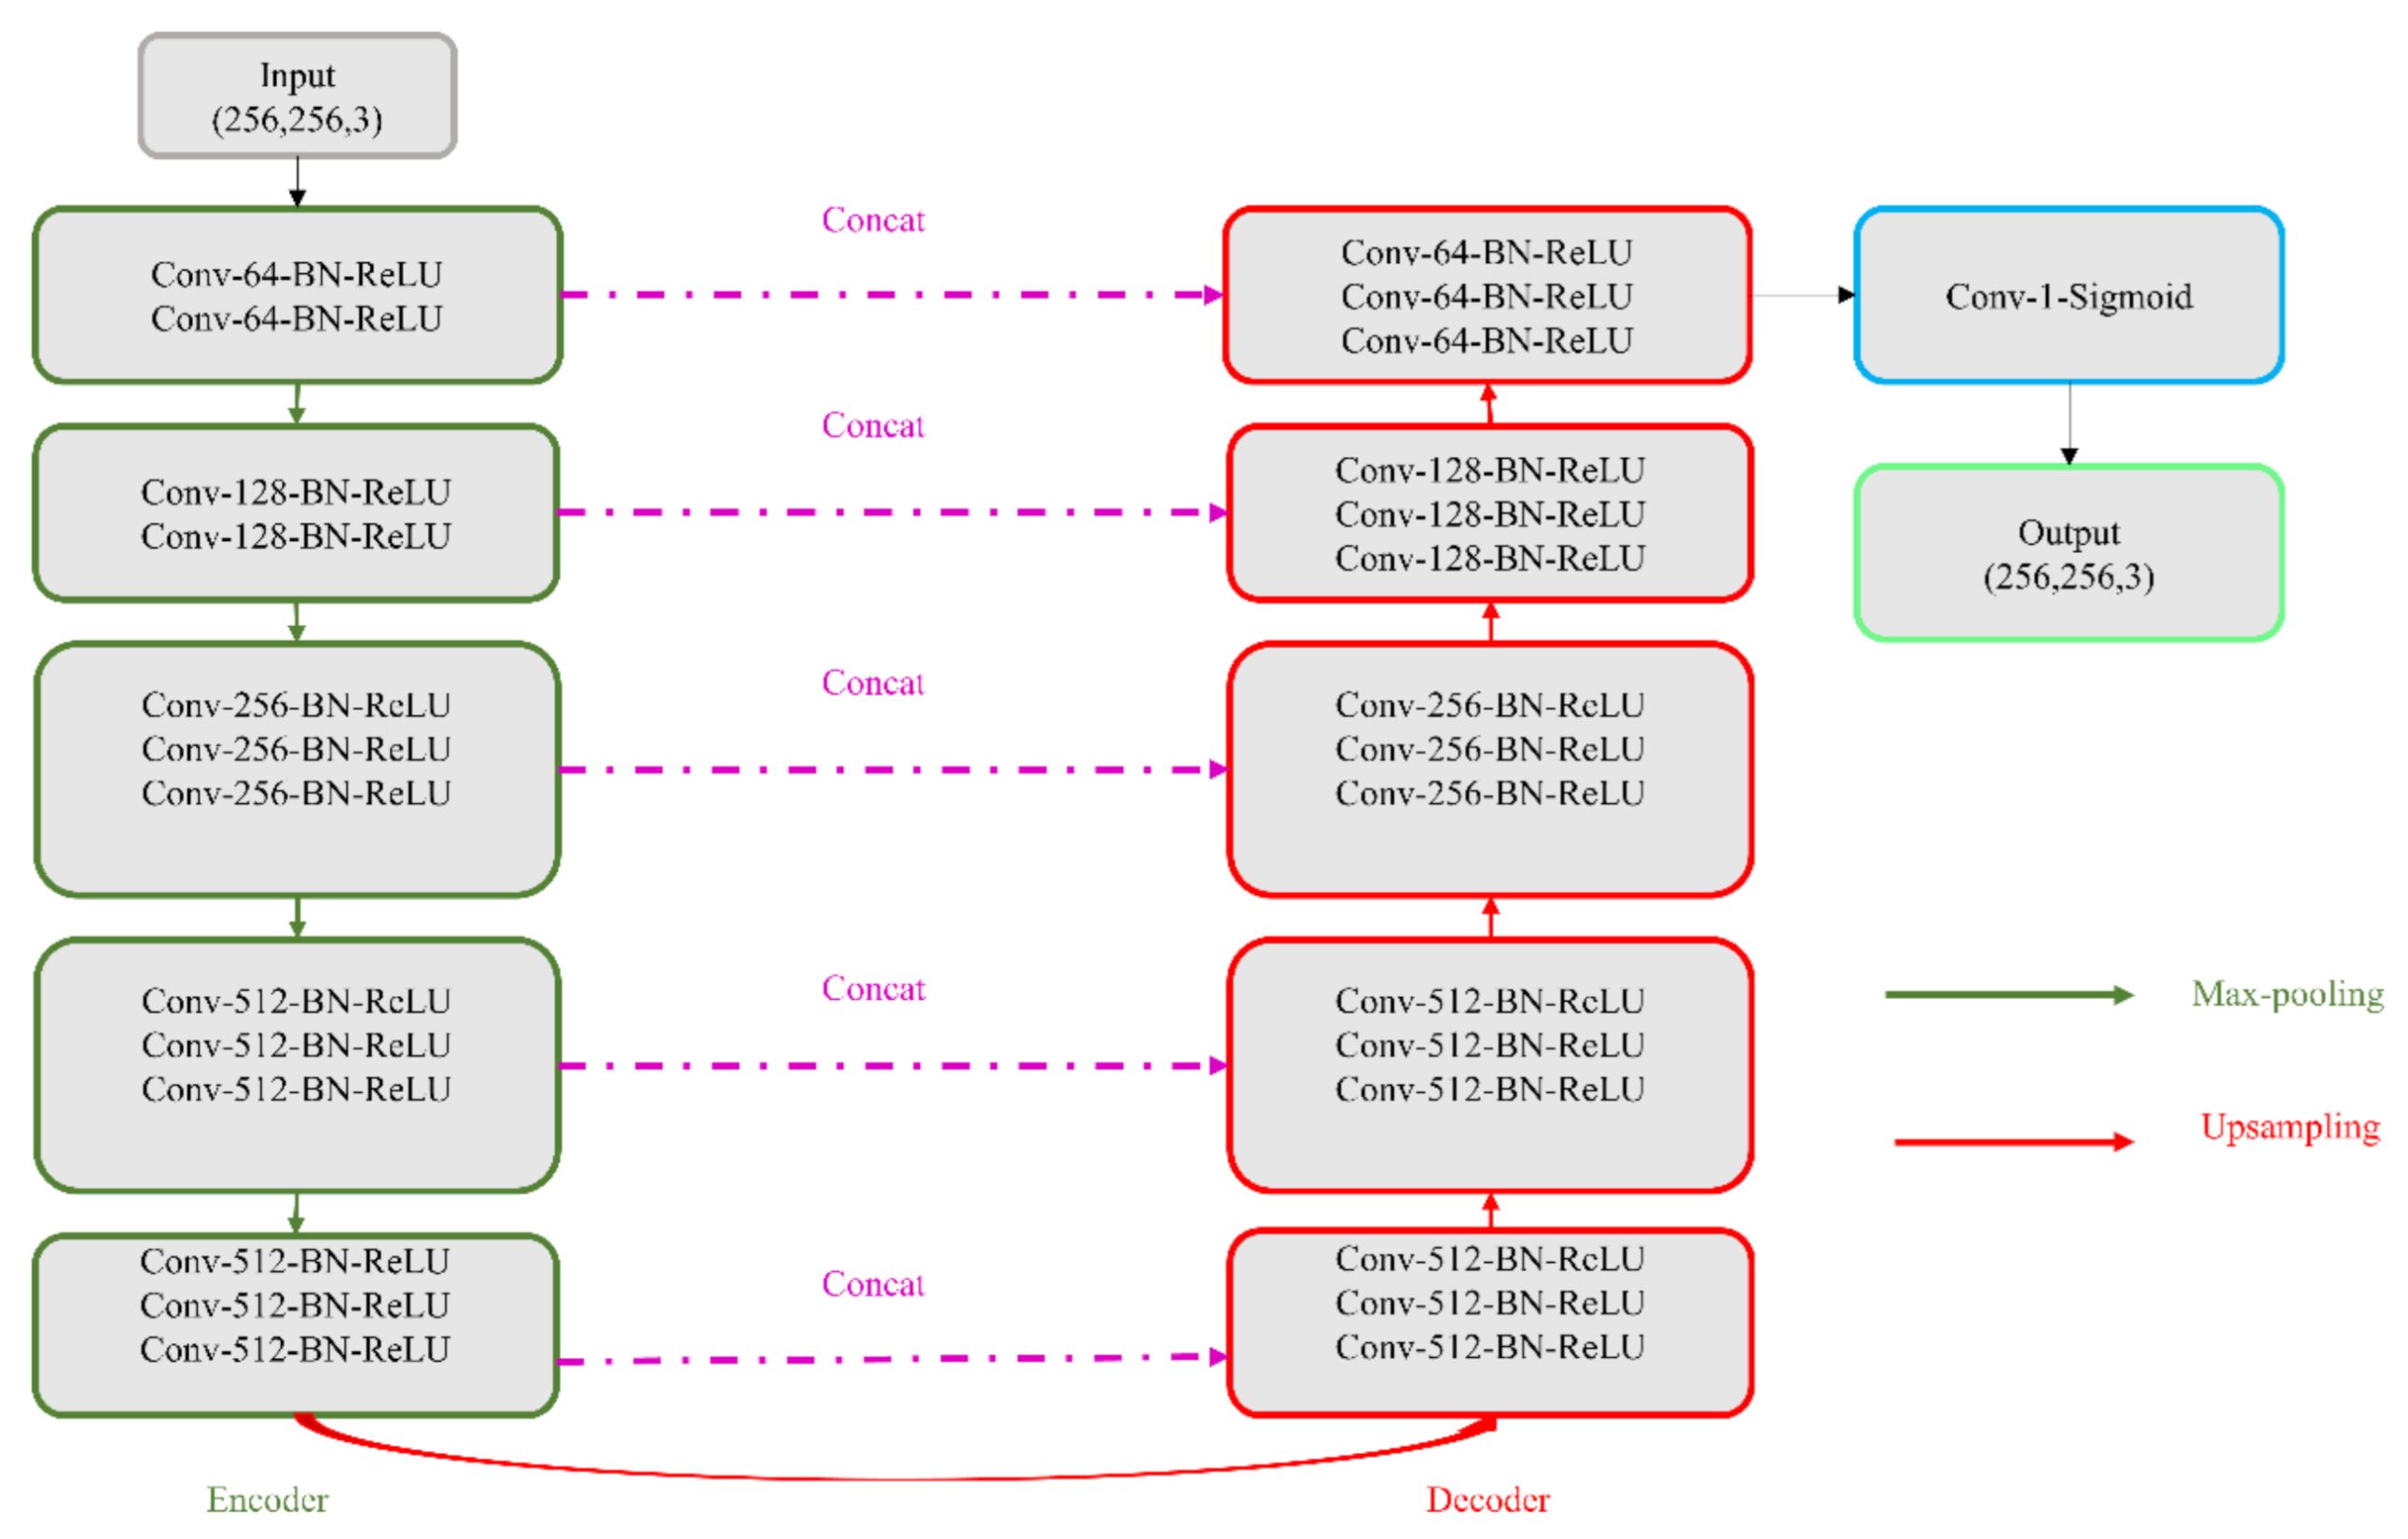

The U-Nets are one of the most powerful CNN models that are used for precise and accurate segmentation of medical images [

20]. The principal advantage of U-Net is that it can handle data scarcity and learn from small training sets. The U-Net has a U-shaped architecture. It is composed of an encoder/contracting path and a decoder/expanding path and performs pixelwise class segmentations. The feature maps from the encoder’s various levels are passed over to the decoder to predict features at varying scales and complexities.

In this study, we propose CXR modality-specific VGG-16 and VGG-19 U-Nets, referred to as VGG-16-CXR-U-Net and VGG-19-CXR-U-Net models. These models use the CXR modality-specific pretrained VGG-16 and VGG-19 models from

Section 2.3 as the encoder backbone. The architecture of the VGG-16-CXR-U-Net and VGG-19-CXR-U-Net models are shown in

Figure 3. The encoder of the VGG-16-CXR-U-Net and VGG-19-CXR-U-Net models are each made up of five convolutional blocks, consisting of 13 and 16 convolutional layers, respectively, following the original VGG-16 and VGG-19 architecture. The green downward arrow at the bottom of each convolutional block in the encoder designates a max-pooling operation (2 × 2 filters, 2 strides) to reduce image dimensions. The decoder of the VGG-16-CXR-U-Net and VGG-19-CXR-U-Net models comprises five convolutional blocks and consists of 15 convolutional layers. The upward red arrow at the top of each convolutional block in the decoder signifies an upsampling operation that performs transposed convolutions to restore the image to its original dimensions. Each convolutional layer in the encoder and decoder is followed by batch normalization (BN) and ReLU activation. The pink arrow signifies skip-connections that combine the corresponding feature maps and restores the original image dimensions. Sigmoidal activation is used at the final convolutional layer to predict binary pixel values.

We evaluated the segmentation performance of the VGG-16-CXR-U-Net and VGG-19-CXR-U-Net models and other SOTA U-Net variants, including the standard U-Net, V-Net with ResNet blocks, improved attention U-Net, ImageNet-pretrained VGG-16 U-Net, and VGG-19-U-Net toward lung segmentation.